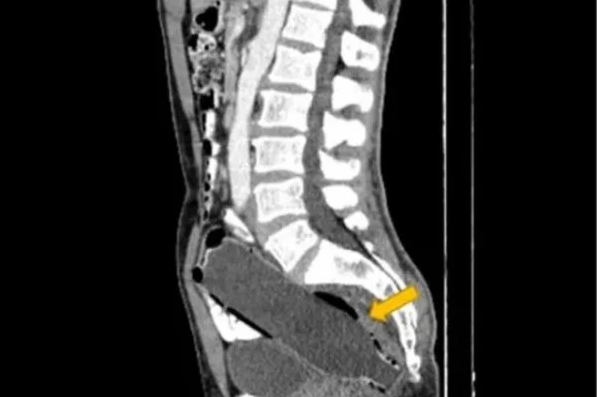

Médicos encontram garrafa de água em paciente com intestino preso

Um homem iraniano de 50 anos foi levado ao hospital pela mulher depois de relatar falta de apetite, dores no estômago e constipação. O paciente foi submetido a uma tomografia computadorizada, que revelou o motivo do desconforto: uma garrafa plástica de 250ml introduzida no reto.

O objeto foi encontrado na região pélvica do paciente, a 10 milímetros da abertura do ânus, e estava alocada entre o reto e o cólon, que faz parte do intestino grosso.

Os médicos disseram que o homem estava extremamente envergonhado com a situação. “Por causa do constrangimento e do medo da esposa, ele não forneceu o histórico do que havia acontecido para explicar a presença do objeto no reto e chegou à emergência do hospital tardiamente”, afirmaram no relato de caso publicado na revista Clinical Case Reports.

Apesar da situação embaraçosa, o intestino do homem não foi danificado pela presença da garrafa de água. O paciente foi levado diretamente à sala de cirurgia, onde foi anestesiado e teve o objeto removido com uma pinça cirúrgica, sem rupturas ou sangramento.